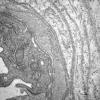

VASCULAR

Hypoxia-Ischemia, fetal-neonatal

White Matter (11)